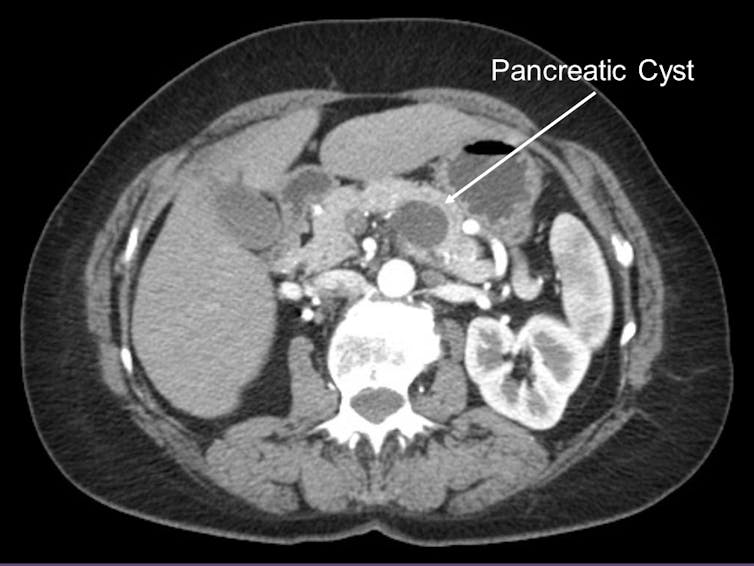

Our last bit of insight came from looking at the genomic changes in pancreatic cyst fluid. About 15 percent of pancreatic cancers are known to arise from pancreatic cysts, or fluid collections within the pancreas. Pancreatic cysts are often identified on routine abdominal imaging and, therefore, amenable to early detection. Because early detection of pancreatic cancer is an important cornerstone to improving patient survival, my team examined those pancreatic cancers arising from pancreatic cysts.

Pancreatic cysts, however, are very common in the U.S. population. In fact, 1 to 2 percent of Americans who undergo an abdominal scan are found to have a pancreatic cyst. Certainly, not all pancreatic cysts will progress to pancreatic cancer and, therefore, tests to detect a pancreatic cancer arising within a pancreatic cyst early is needed.

In 2017, our team at UPMC reported the creation and validation of a clinically available test to evaluate patients with pancreatic cysts called PancreaSeq. PancreaSeq evaluates the genetic changes in pancreatic cyst fluid to identify those cysts that are likely to transform into pancreatic cancer. It is used by several institutions throughout the U.S.

Among the 3,594 pancreatic cancers profiled for our recent study, we identified key genetic alterations among pancreatic cancers arising from pancreatic cysts that could be incorporated into PancreaSeq and improve its ability to detect pancreatic cancer early.